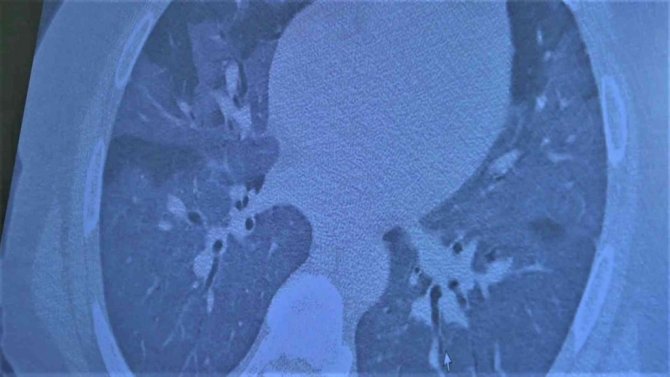

Koronadan dolayı yaşam mücadelesi veren aşısız bir kişini akciğerlerinin inceleyen Özkaya, "45 yaşındaki bir hastamız aşı olmaya zamanı olmadığı için yaygın akciğer tutulumuyla geldi. Aşı hastalığa yakalanmanızı önlemeyecek ama hastalığa yakalandığınızda bu tabloya girmenizi önleyecek. Bu hastamızı maalesef kaybetmek üzereyiz. Pişman olmamak için herkesin aşı olmasını istiyoruz. Bu hastamızı yaygın akciğer tutulumu ile hayat mücadelesi veriyor" şeklinde konuştu.